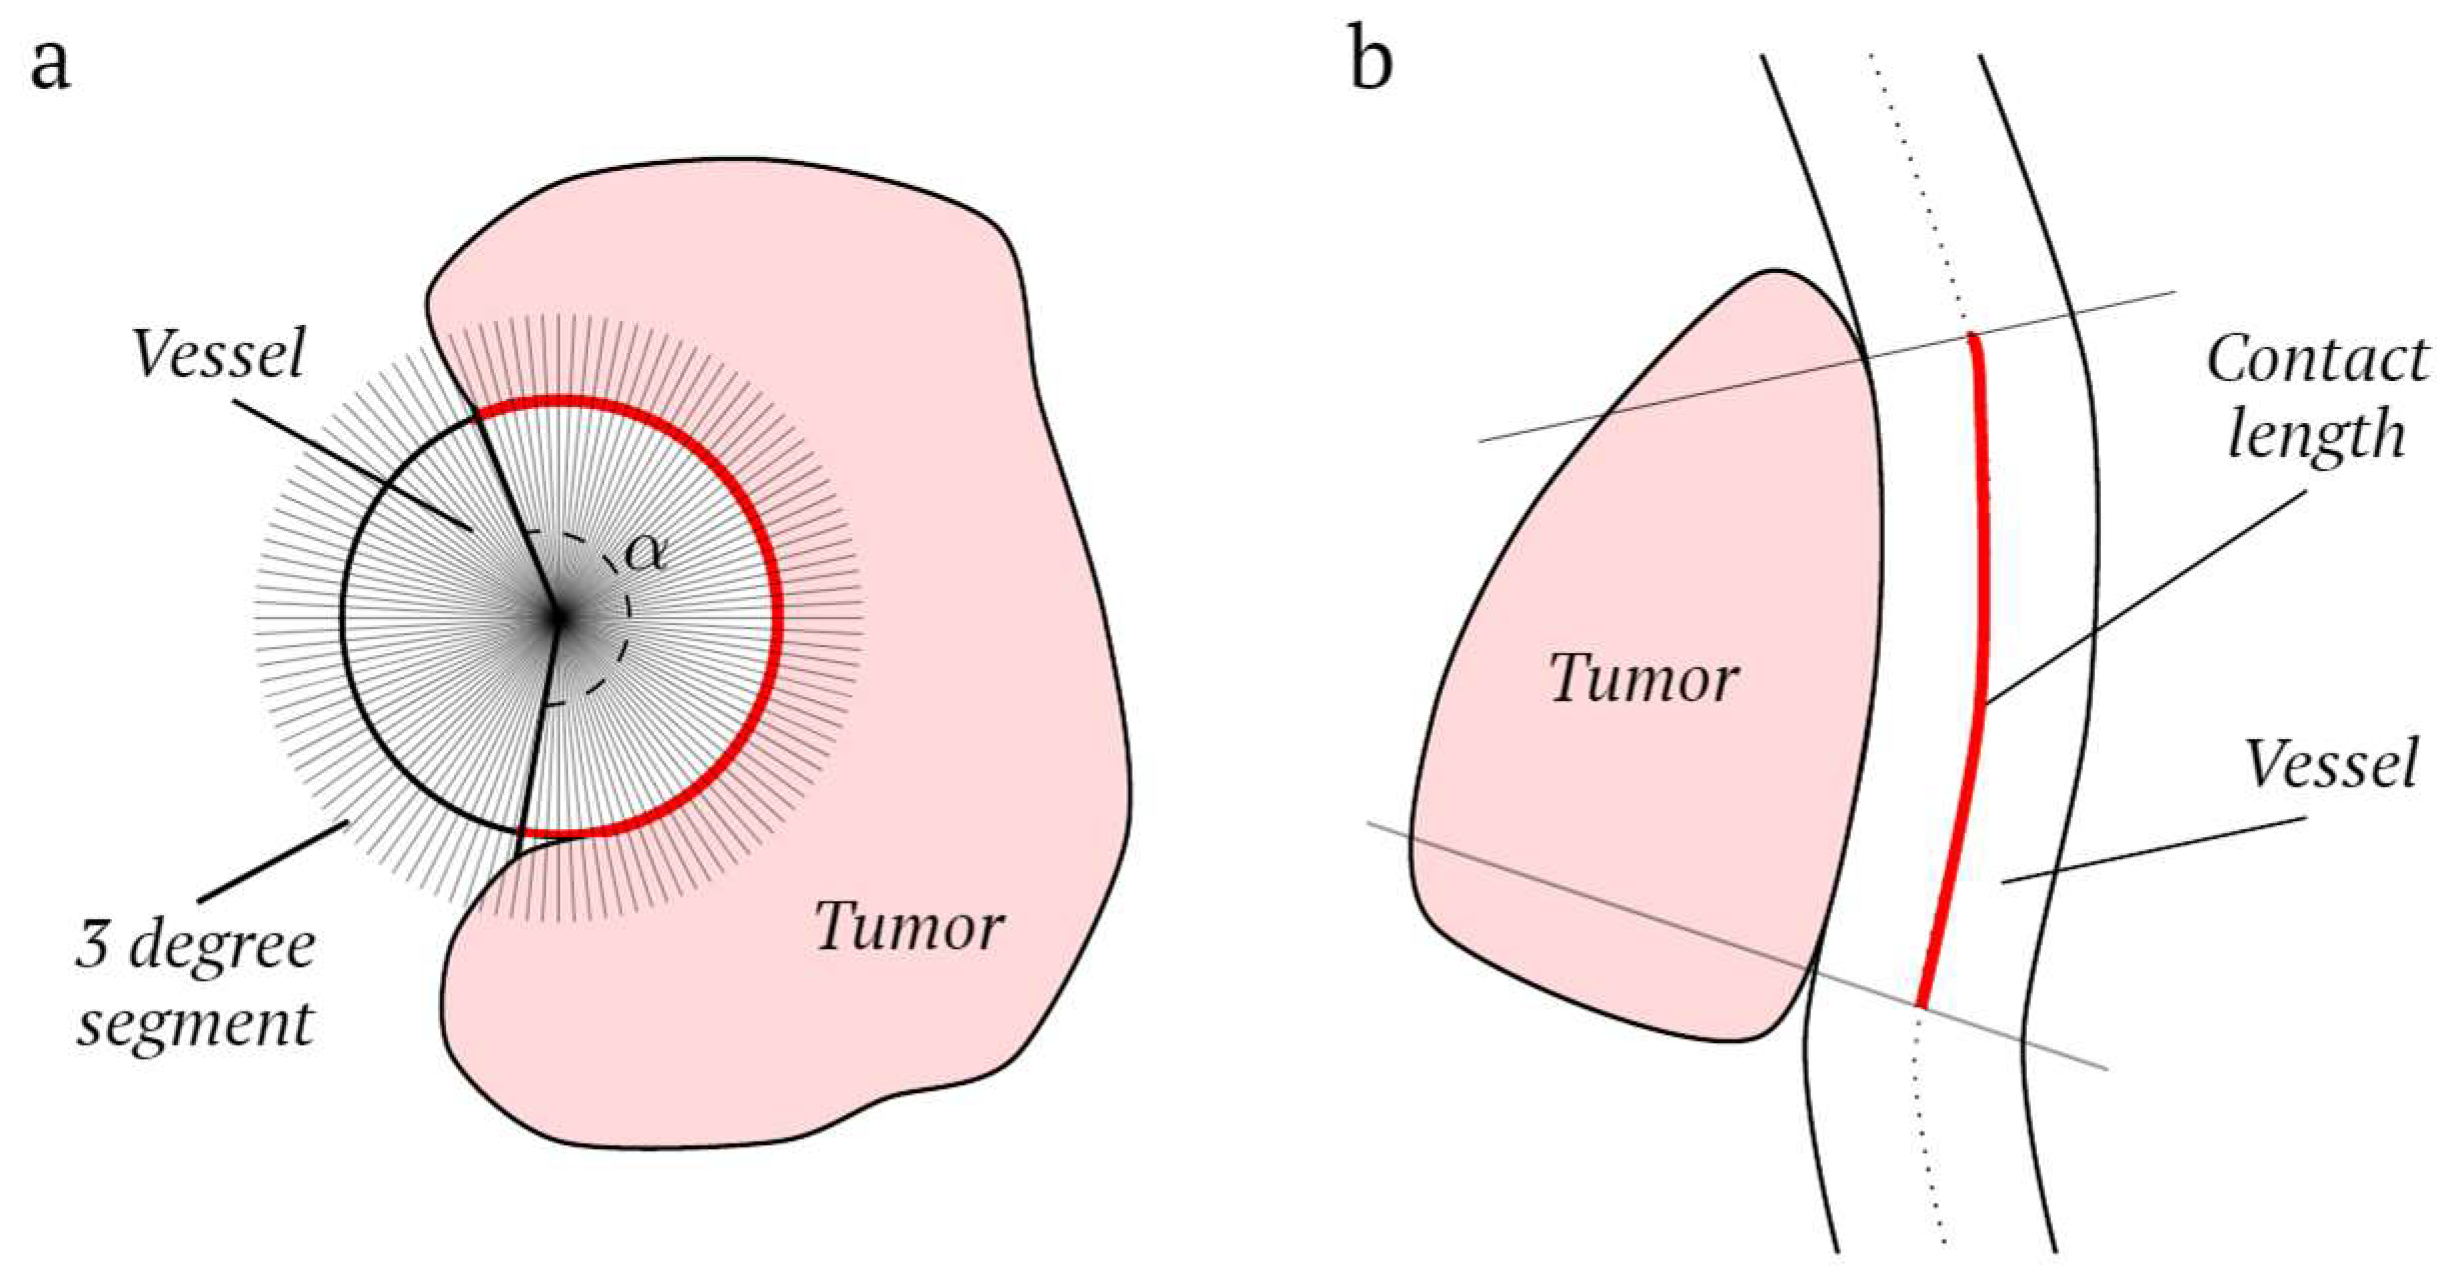

2.5. Vessel Features